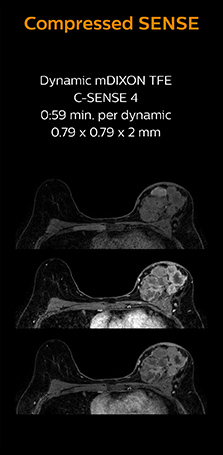

Identification of small breast lesions requires high resolution

Dr. Koyama says that he used to believe that high resolution MRI at 1.5T required long scan times, and SNR was low. “With Compressed SENSE, however, it is possible to acquire high quality images, even with higher Compressed SENSE factors, so in a quite short time.”

“In breast scanning, high resolution is important to help me identify very small mammary lesions, so, we need high spatial resolution in 2D T1- and T2-weighted images, as well as a short scan time. Compressed SENSE has allowed us to increase spatial resolution, which benefits our diagnostic confidence.”

Dr. Koyama says that a C-SENSE factor of 4.0 was chosen to increase their spatial resolution in 3D dynamic breast scanning. “In addition to a high temporal resolution, we also require high spatial resolution, which helps us to see details of the internal structure of the lesion and to see lesions separately from normal anatomic structures. We can also see if a lesion extends into adjacent organs and anatomic structures.”

3D MRI with Compressed SENSE of patient with breast cancer

This patient underwent MRI on Ingenia 1.5T with Compressed SENSE. Compressed SENSE was used to reduce the scan time in order to decrease the time that the patient may experience discomfort and pain, both of which may lead to patient motion. The 3D BreastVIEW and 3D high resolution mDIXON images – both mDIXON contrasts are acquired in the same exam – show high quality images even with the shorter scan time. The spatial resolution of the dynamic scan with Compressed SENSE is higher than in the previous protocol (not shown) which allows for better visualization of the lesion with respect to the muscles of the thoracic wall and better delineation of small structures.

For breast imaging, a fast, high resolution scan can be important for a female patient having to lie in an uncomfortable, face-down position in the scanner. Compressed SENSE also helps us to obtain higher1 quality images using 3D BreastVIEW and 3D high resolution mDIXON sequences in the same examination time as in our previous exam protocol.